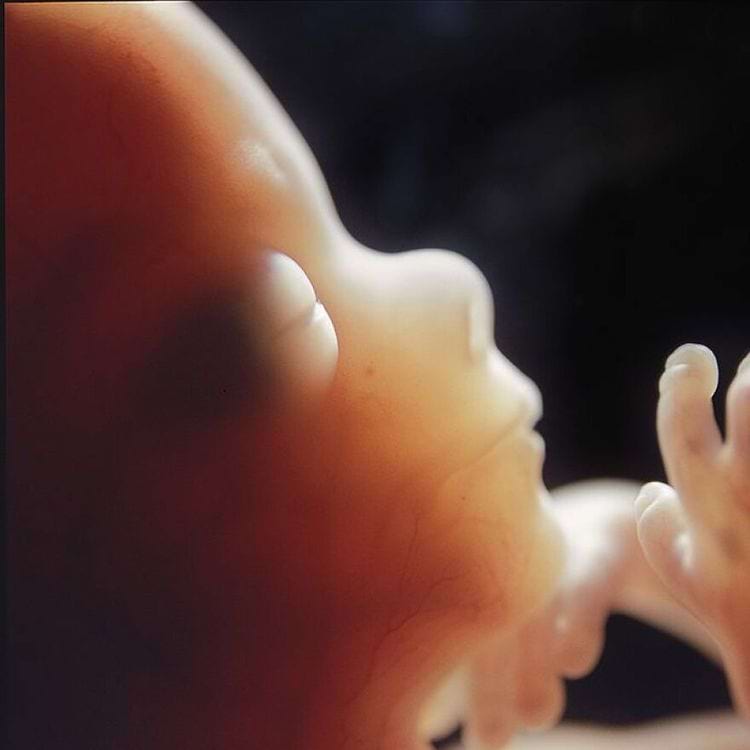

Знаменитый снимок «Плод на 18 неделе», 1965 год